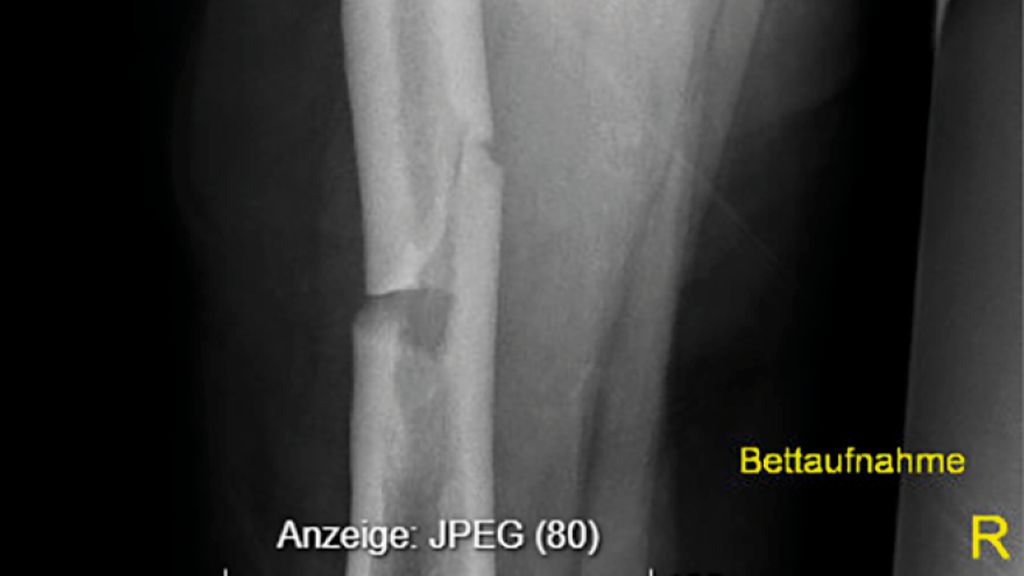

Dr. Bernhard Rintelen von der 2. Medizinischen Abteilung am NÖ. Landesklinikum Weinviertel/Stockerau präsentierte den Fall einer 72-jährigen Patientin mit Zustand nach Hysterektomie mit Salpingektomie sowie nach einem nicht metastasierten Kolonkarzinom. Nach einer Netzhautablösung bestand eine deutliche Visusbeeinträchtigung; bei Vorhofflimmern wurde die Patientin mit einem DOAK antikoaguliert. Die Familienanamnese war hinsichtlich Frakturen unauffällig. Mit 70 Jahren hatte die Patientin eine Femurfraktur erlitten. Die aktuelle Vorstellung erfolgte aufgrund multipler Wirbelkörperfrakturen sowie einer niedrigtraumatischen Sakrumfraktur. In der Bildgebung zeigten sich innerhalb weniger Monate wiederholt neue Einbrüche weiterer Wirbelkörper, das Labor war unauffällig. Eine Osteoporose war bekannt, insgesamt hatte die Patientin über 14 Jahre Bisphosphonate erhalten (9 Jahre oral, 5 Jahre Ibandronat i.v.). Eine osteoanabole Therapie war geplant; Teriparatid wurde aufgrund der Visusprobleme abgelehnt, weshalb eine Behandlung mit Romosozumab erfolgte. Nach einem Jahr zeigte sich eine Konsolidierung ohne weitere Wirbelkörperfrakturen.